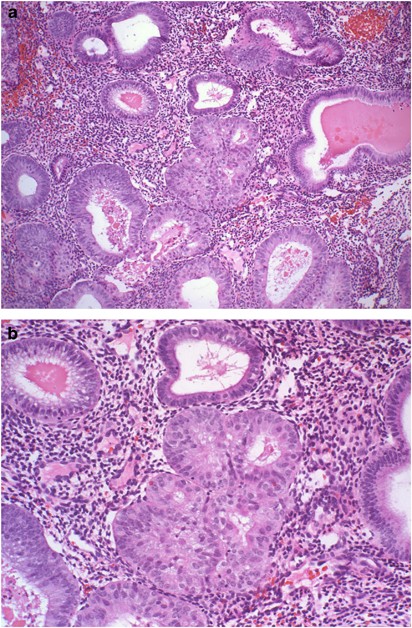

Cases with the diagnosis of complex atypical endometrial hyperplasia on endometrial curettage/biopsy and subsequent hysterectomy were examined for the presence of AIS. The cases were seen at New York University Medical Center, New York; North Broward Medical Center, Deerfield Beach, FL, and at Thomas Jefferson University Hospital, Philadelphia, PA. The cases were retrieved by searching for cases with the diagnosis of complex endometrial hyperplasia in the computerized records in each facility. The cases were sequential and seen from 2003 to 2006. Scant or otherwise suboptimal specimens were excluded from the study. The presence or absence of AIS was diagnosed at each facility based on review of the case by individual pathologists. Cytologic features were not included as a criteria for exclusion of a case, but none of the cases had grade III nuclei. The review of biopsies was done blindly without knowledge of the hysterectomy findings. Hysterectomy diagnosis of record was used. AIS was defined as foci of back-to-back arrangement of glands or foci of cribriform arrangement of glands composed of at least four glands and smaller than 2.1 mm in diameter (Figures 1, 2 and 3). Foci with marked glandular crowding, where stromal cells were readily identified between adjacent glands, were not considered AIS. Artifactual cribriform arrangement of glands such as appearance can be seen when there is squamous metaplasia or morule formation in endometrial glands, and these were also not included as AIS (Figure 4). The size of the largest AIS focus was noted in each case. Follow-up findings in the two groups of patients with and without AIS were analyzed, including the presence or absence of carcinoma in the hysterectomy specimen, the grade of the carcinoma and the depth of myometrial invasion.